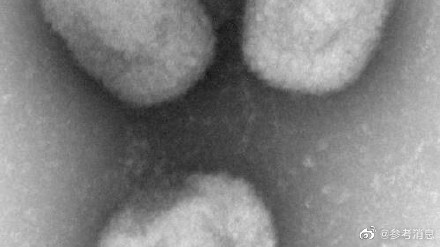

日媒:日本发现首例猴痘病例

据日媒25日报道,日本厚生劳动省表示,日本国内发现首例猴痘确诊病例。当地时间25日,日本外务省针曾对猴痘疫情发布全球一级旅行警告。 (中国新闻网)